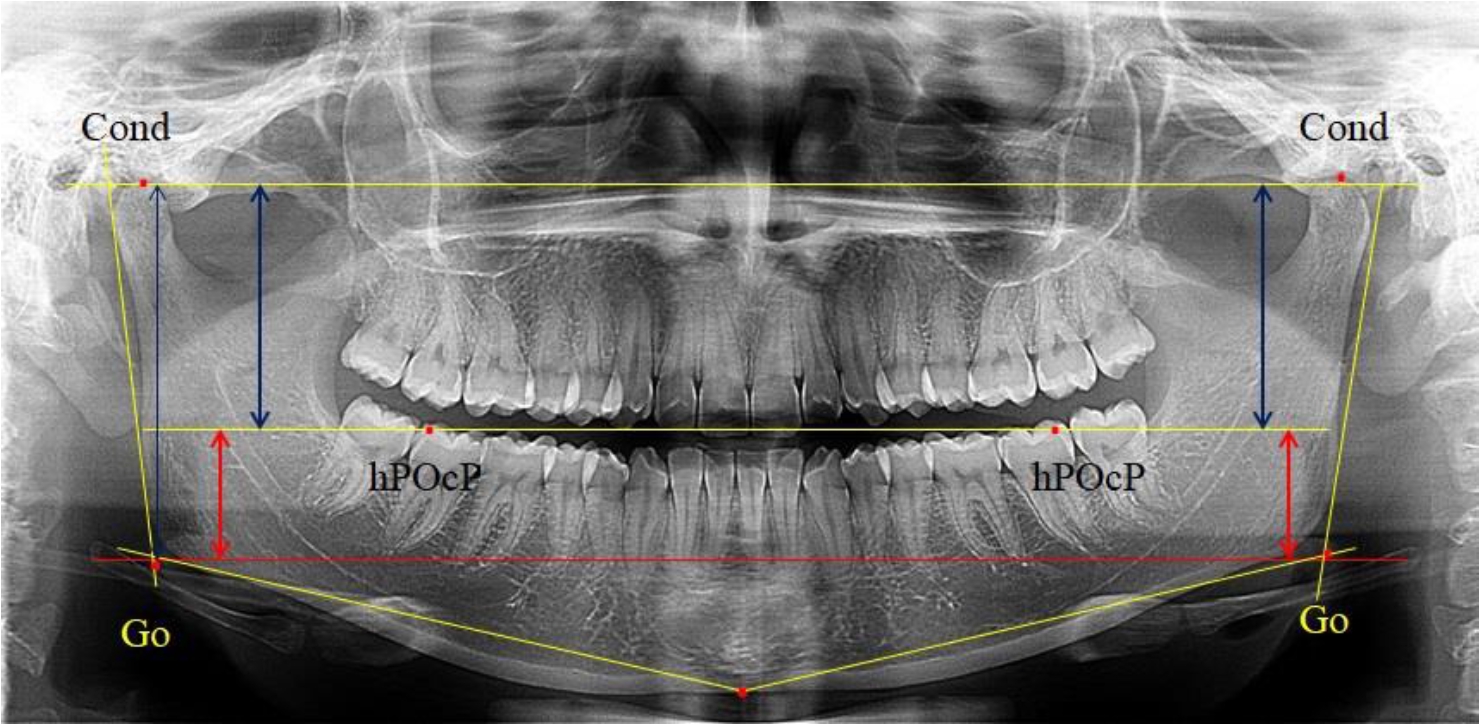

В 1-ю подгруппу были включены 36 комплектов телерентгенограмм и ортопантомограмм [или (48,65 ± 5,81) % от общего количества], на которых средняя величина отношения верхней части ветви к нижней составляла 1,95 ± 0,03, что соответствовало показателям, полученным по группе в среднем, но с меньшим показателем ошибки среднего значения. Визуально верхняя окклюзионно-суставная часть выглядела вдвое больше нижней окклюзионно-гониональной (рис. 2). При этом высота ветви составляла (62,09 ± 1,22) мм. Максимальная высота была 71 мм, а минимальная – 55 мм. Высота верхней части составляла (41,02 ± 0,77) мм, а высота нижнего отдела ветви была (21,09 ± 0,51) мм.

Рис. 2. ОПТГ пациента 1-й группы с оптимальным коэффициентом соотношения частей ветви нижней челюсти